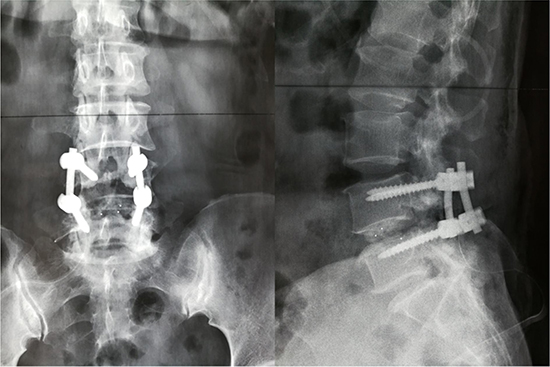

We retrospectively collected medical records of elderly patients (aged ≥ 60 yrs) undergoing lumbar fusion surgery between 01/2013 and 01/2015 in our spinal department. Figure 1 shows the postoperative X-ray image of lumbar fusion surgery. Some of the identified patients randomly underwent systematic training of lower-limb rehabilitation gymnastics (intervention group), the others not (control group). As Figure 2 showed, 612 cases were initially identified, and finally 540 patients were included and admitted to this study. Inclusion criteria of the present study were as follows. 1- All patients have undergone lumbar spinal fusion surgery. 2- Preoperative lower-limb muscle strength was grade III or grade IV (because our lower-limb gymnastics is not suitable for the patients under grade II and meaningless to those grade V). 3- No history of other operations were on the lower-limbs. 4-No neuromuscular disease were on the limbs. 5-No pathologicalmyelitis or neuropathy existed. 6-All the patients have been excluded from lower-limb DVT by preoperative ultrasonography. Patients who did not have regular follow-up visits or had systemic disorders were also excluded.

Figure 1: Postoperative X-ray image of lumbar fusion surgery.